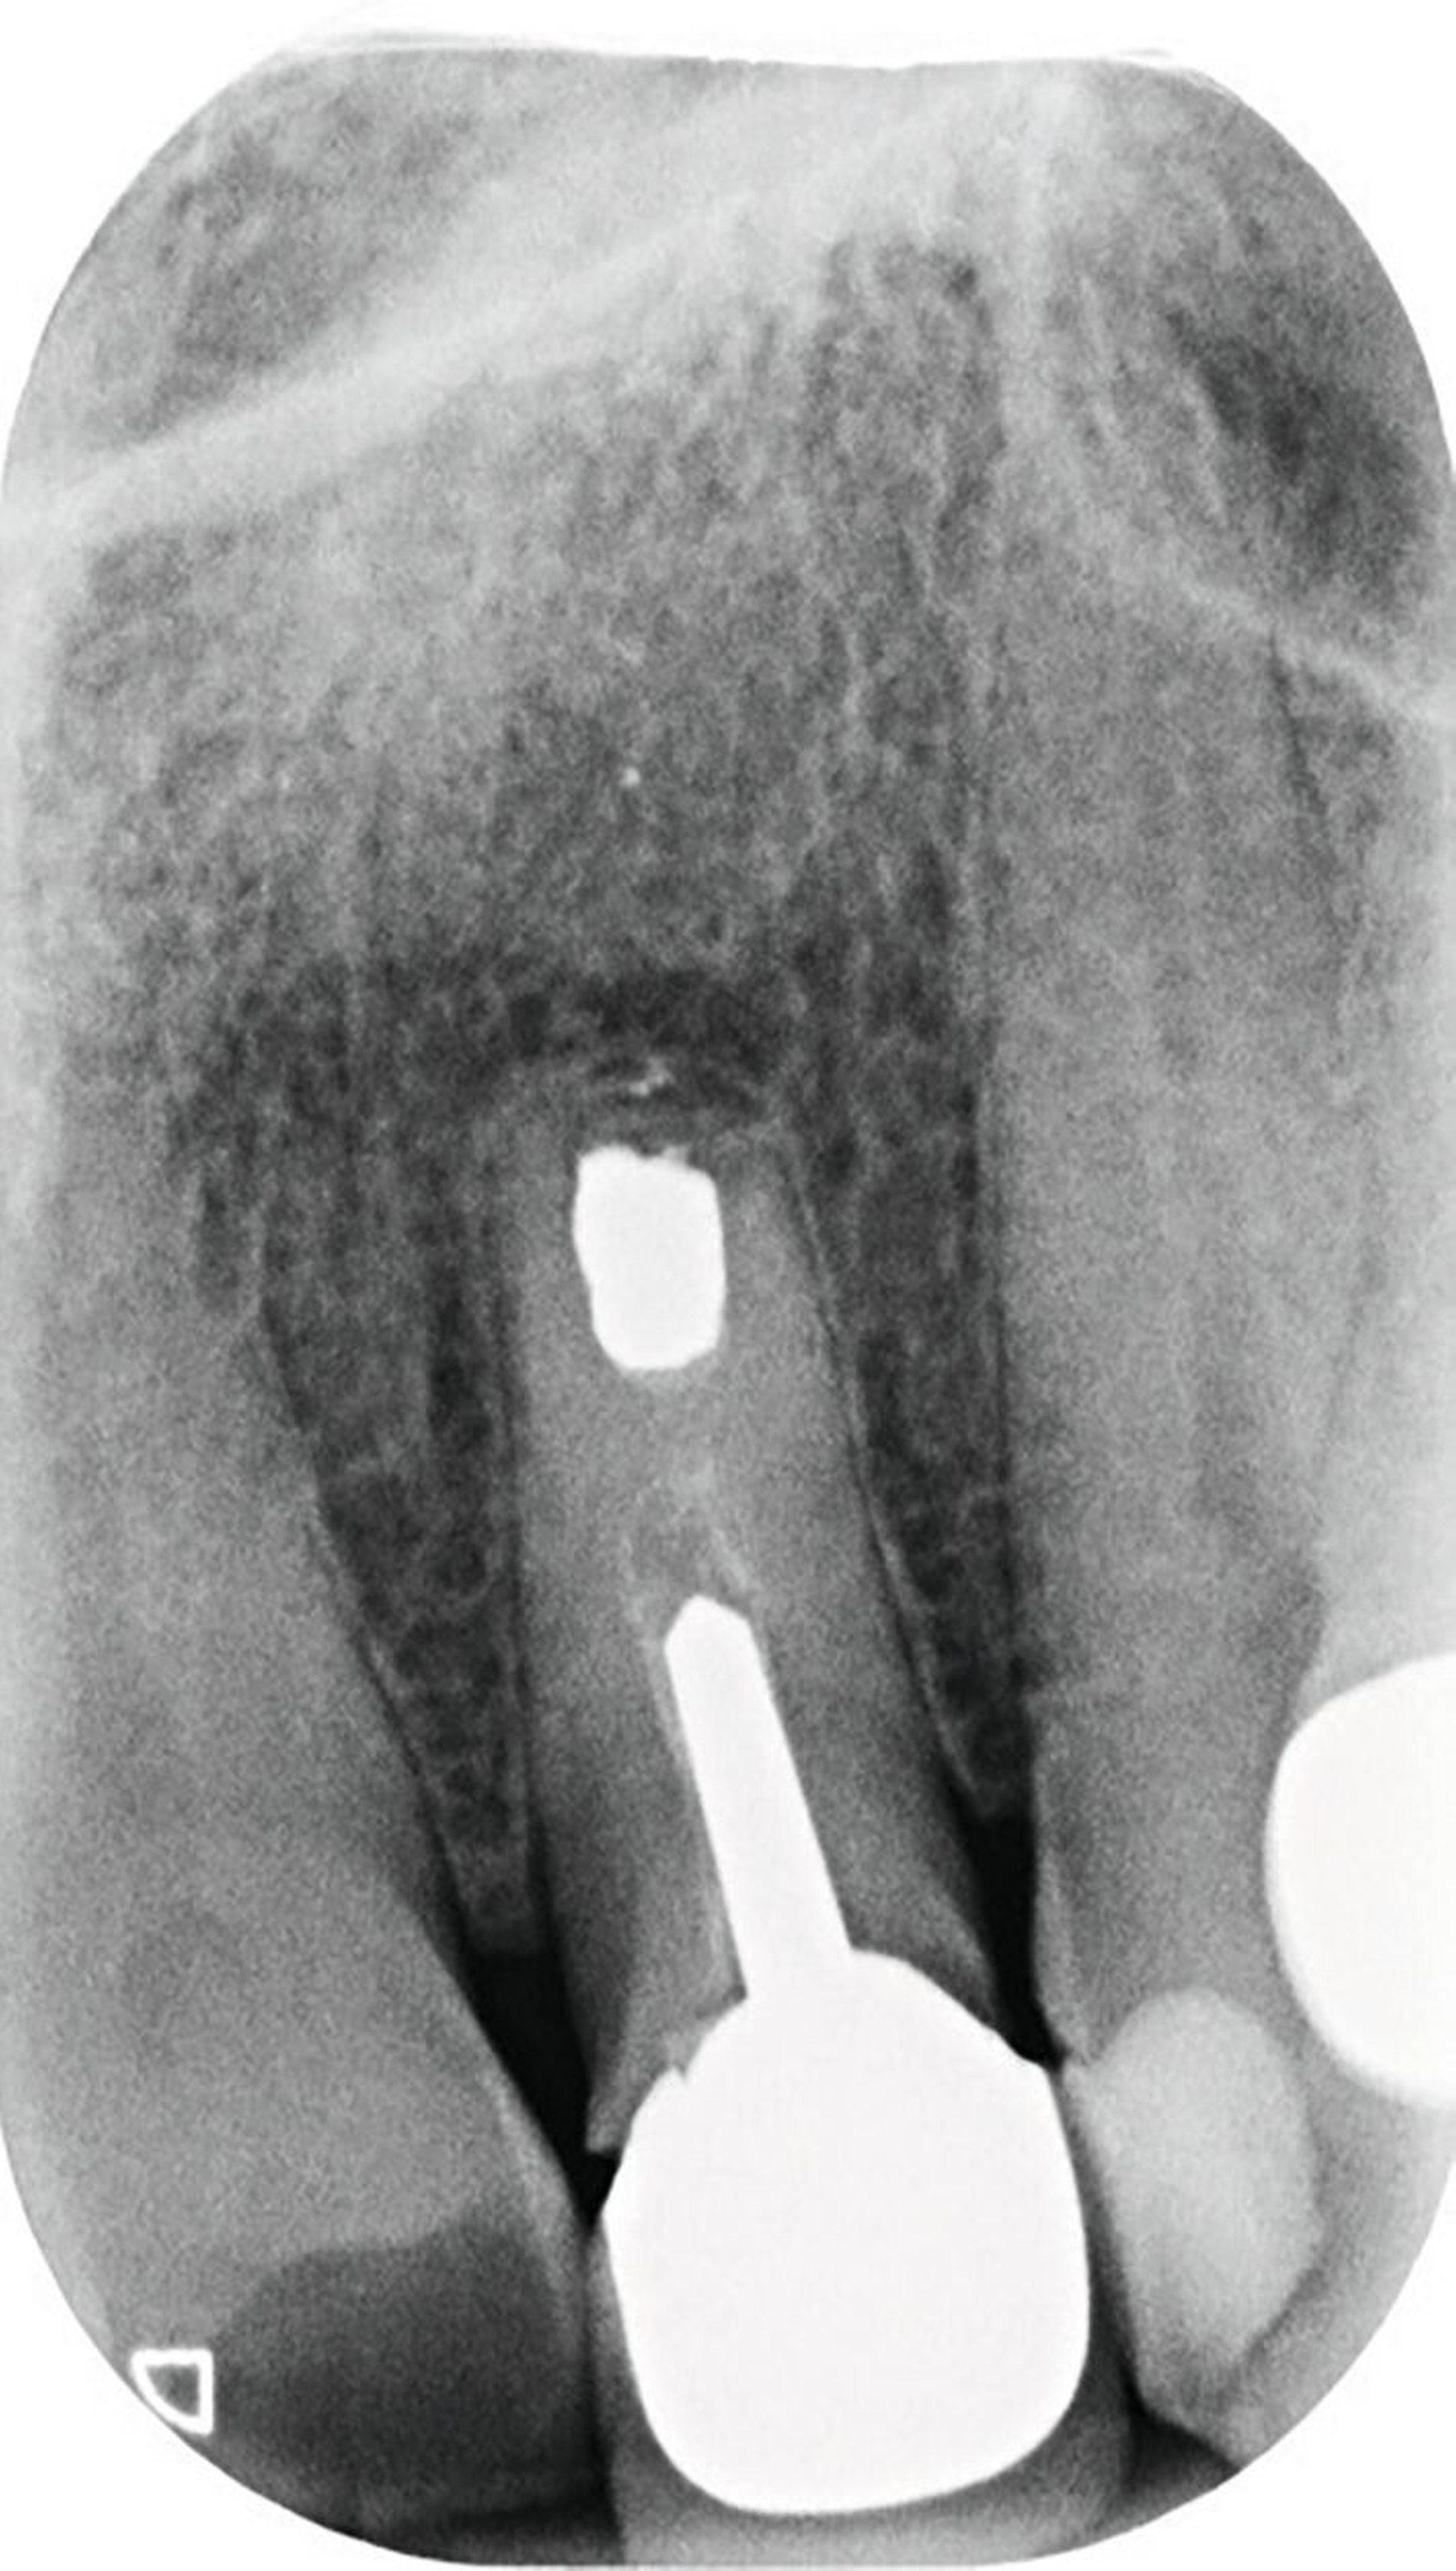

Vor 25 Jahren hatte der Patient ein Frontzahntrauma an Zahn 22 erlitten, der daraufhin mit einer Wurzelspitzenresektion und einer retrograden Amalgamfüllung versorgt worden war (Abbildung 3a). Dabei war die Zahnkrone mit einer keramisch verblendeten Stiftkrone aus Nichtedelmetall rekonstruiert worden, die nun aufgrund von Sekundärkaries insuffizient und gelockert war, jedoch keine Beschwerden verursachte. Klinisch wies der Zahn eine sehr kurze klinische Krone ohne ausreichendes Ferruledesign auf (Abbildung 5a) [Naumann et al., 2018a; Naumann et al., 2018b]. Neben dem Verdacht auf einen obliterierten mittleren Wurzelkanalabschnitt gab es röntgenologisch keinen Hinweis auf apikale Osteolysen oder parodontale Auffälligkeiten (Abbildung 3b). Der Patient entschied sich trotz des erhöhten Zahnhartsubstanzdefekts für den Zahnerhalt durch einen adhäsiv verankerten Kompositaufbau.

Für die restaurative Therapie von Zahn 22 wurde die alte Stiftkrone entfernt und die Stiftbohrung an die neue Indikation angepasst (Abbildungen 5a und 5b). Die Zahnkrone wurde dabei in drei Phasen wiederhergestellt: adhäsives Zementieren eines konfektionierten Glasfaserstifts, Stumpfaufbau und Modellation einer direkten Kompositkrone mit Silikonschlüssel, Frontzahnmatrize für komplexe Situationen und Schneepflugtechnik (Abbildungen 5c bis 5e) [Urkande et al., 2023; Amaro et al., 2021; Frese, 2020; Mannocci et al., 2002; Dimitrouli et al., 2011; Opdam et al., 2003]. Im Röntgenkontrollbild zeigt sich ein suffizienter Stiftaufbau (Abbildung 6).